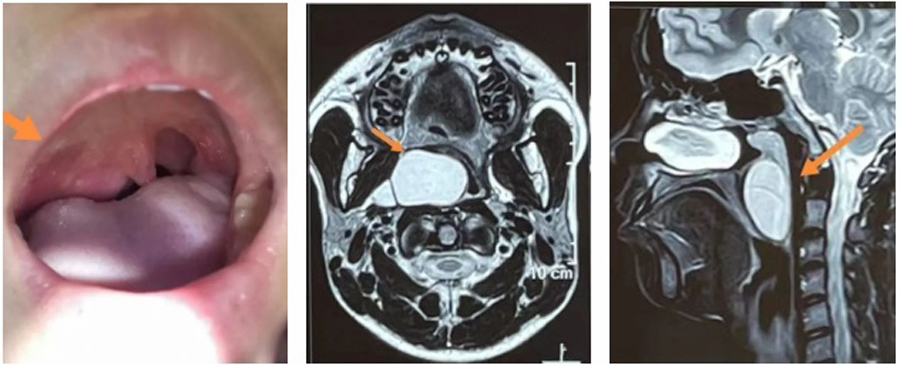

小君因为咽部异物感,右侧面部膨隆来啪啪网 就诊,平日并没有咽痛、吞咽困难、消瘦等。在检查中,医生发现,小君右侧软腭明显凸出,边缘可见肿物向内下方膨隆、悬雍垂(小舌头)整体左移、腭弓向内下方偏移,鼻咽镜检查发现肿物上极已达鼻咽部后鼻孔层面,下极到喉部会厌缘平面,跨度大,基地宽。根据小君临床表现,估计肿物生长已数年之久,为明确肿物性质,医生立即进行了进一步检查。通过增强CT、核磁检查明确了肿物的边界,上边界达鼻咽顶、下边界在声门上,外边界与颈外侧动静脉相毗邻、内边界将咽部内侧壁完全向内下方挤压。影像显示肿物边界清晰,结合其临床表现,考虑恶性可能性不大,但由于肿物巨大,向内侧已到中线位置,向外侧,小君的右侧面部已出现略向外膨隆状态,手术迫在眉睫。

确定手术治疗后,张薇副院长和团队根据检查情况,积极制定手术方案。手术最大的风险在于肿物的位置特殊,与颈内动静脉关系紧密,稍有不慎损伤,后果不堪设想。手术入路是经内镜从口咽进入?还是经颈外侧切口进入?张薇副院长仔细分析了手术方案:如果从咽部进入,可以避免皮肤切口造成的颈部瘢痕,但对术者的手术能力要求很高,需要内镜辅助,尽量清除囊壁的同时要注意保护好血管;如果从颈外侧进入,切口较大,造成颈部瘢痕,可能影响患儿颈部美观,甚至影响升学,且手术需跨越整个动静脉区,才能到达肿物的位置,并且有形成咽瘘、神经血管损伤等并发症。为避免颈部巨大瘢痕对患儿的影响,儿医团队还是决定经口咽入路,迎接挑战,尽最大努力,保患儿安康。

肿物外壁彻底打开,吸引出大量棕黄色黏稠物,内镜探入腔内观察,可见数个分隔,非常深,直逼颈外侧,其中一个囊腔外侧壁与颈内动静脉完全呈现“共壁”状态,通过内镜,菲薄的囊壁下清晰可见粗大的颈内静脉血管及不断搏动的颈内动脉。这一情况,着实让团队成员心头一紧。安全起见,张薇副院长果断决定保留“共壁”部分的囊壁,剥离、切除囊肿底壁的其他部分。